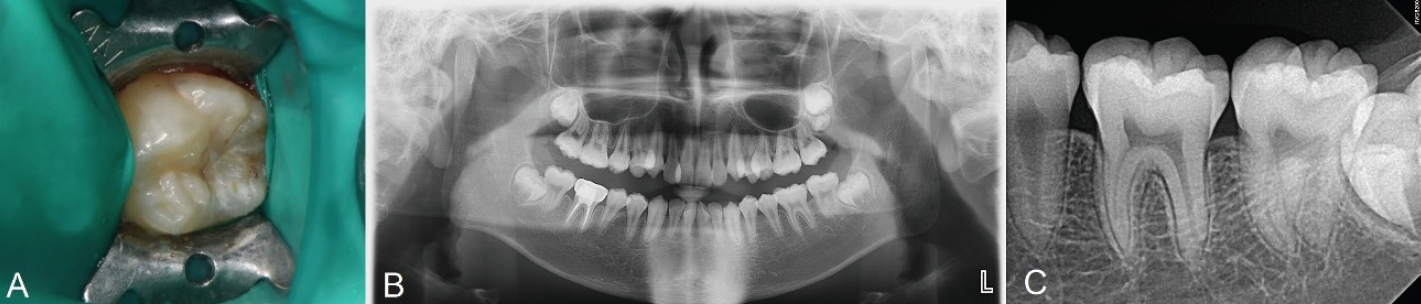

치료 전 1:100000 epinephrine을 포함하는 2% Lidocaine(Yuhan Corporation, Seoul, Korea)으로 우측 하악 구치부 전달마취를 시행하였다. 러버댐을 이용하여 격리를 시행하고 저속핸드피스 및 주수 하에 prophy brush를 사용해 좌측 하악 제2대구치의 교합면을 세정하였다. 이후 유동형 복합레진(Tetric N-Flow, Ivoclar Vivadent, Schaan, Liechtenstein)을 교합면에 적용하고 마이크로브러시의 팁을 손잡이로 사용하기 위해 복합레진에 위치시킨 뒤 광중합하여 스탬프를 형성하였다(Fig. 2C).

그 후, 일반적인 와동 형성 프로토콜에 따라 우식 제거를 시행하였다. round diamond bur(BR-31;MANI, Tochigi, Japan)를 이용하여 고속 핸드피스로 주수 하에 우식을 제거하고 class I 형태의 와동을 형성하였다(Fig. 2A). 글라스아이오노머(Ketac Fil Plus Aplicap, 3M ESPE, St. Paul, USA)를 이용해 base 수복을 시행하였다(Fig. 2B). 교합면 와동은 법랑질을 10초간 35% phosphoric acid(Ultra-Etch, Ultradent, South Jordan, USA)로 산부식한 뒤 추가로 상아질에 10초간 더 산부식하고 수세하였다. 약하게 공기를 분사하여 수분을 제거한 뒤 3-step etch-andrinse system인 Adper Scotchbond Multi-Purpose Bond(3M ESPE, St. Paul, USA)의 primer를 microbrush(Microbrush International, Grafton, USA)로 5초간 도포하고 공기 분사 후 adhesive를 microbrush로 5초간 도포하고 공기 분사한 뒤 lightemitting diode(LED) 광중합기(B&Lites, B&L Biotech, Wonju, Korea)로 10초간 중합하였다.

이후 Microhybrid계 복합레진인 Filtek Z250(3M ESPE, St. Paul, USA) 이용해 교합면에서 2mm 아래까지 수복하고 20초간 광중합하였다. 최종 복합레진 적층 전에 다시 복합레진을 적용한 후 테플론 테이프를 교합면에 덮고 마이크로브러시로 만든 스탬프를 정밀하게 위치시켜 가볍게 압력을 주어 눌렀다. 스탬프 및 테플론 테이프를 제거한 뒤 과잉 재료를 레진 기구로 정리한 후 복합레진을 최종 광중합하였다(Fig. 2D). 교합지와 심스탁을 이용한 교합 검사 후 교합 조정을 시행하였다. Sof-lex spiral(3M ESPE, St. Paul, USA)로 수복물 연마를 시행하였다.

Fig. 2.

A. Caries excavation and cavity preparation is done. B. Base restoration with glass ionomer is done. C. Stamp is obtained using flowable resin and microbrush. D. Photograph after applying stamp on teeth. E. Postoperative periapical radiograph